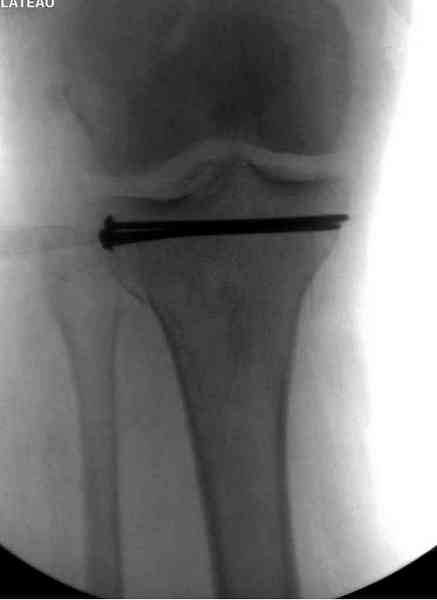

Имя     : 1 lat tib plateau AP.jpg

Тип     : image/jpeg

Размер  : 14431 байтов

Описание: отсутствует

Url     : http://weborto.net:8080/pipermail/ortho/attachments/20100926/dbcec959/attachment-0012.jpg

Основная задача в лечении околосуставных переломов является создание

солидного базиса в субхондральной зоне. Пластина подпорка (Butress)

или субхондральные перкутанные шурупы в виде плота (Raft) для ранних

движении.